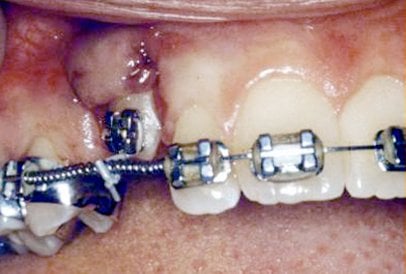

In cases where the eyeteeth will not erupt spontaneously, the orthodontist and oral surgeon will work together to get these teeth to erupt. Each case must be evaluated on an individual basis, but treatment will usually involve a combined effort between the orthodontist and the oral surgeon. The oral surgeon will expose and bracket the impacted eyetooth.

The goal is to erupt the impacted tooth and not to extract it. Once the tooth has moved into its final position, the gum around it will be evaluated. In some circumstances, there may be some minor “gum surgery” required.

The surgery to expose and bracket an impacted tooth is a very straightforward surgical procedure that is performed in the oral surgeon’s office. For most patients, it is performed using laughing gas and local anesthesia. In selected cases it will be performed under IV sedation if the patient desires to be asleep, but this is generally not necessary for this procedure. If the procedure only requires exposing the tooth with no bracketing, the time required will be shortened by about one half. These issues will be discussed in detail at your preoperative consultation with your doctor.